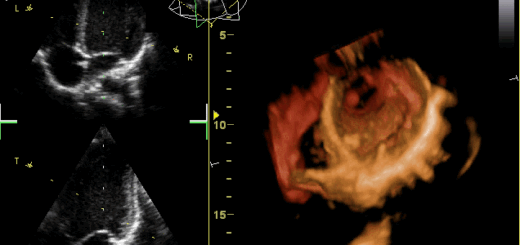

Week5 Day3 心臓内景、縦隔

前説 流路を意識して心腔、弁、流出路をみよう 心エコーの断面がどういう断面か、心臓に照らしあわせよう 冠状静脈洞、上下大静脈の弁は、ヒダ 胸腺は...